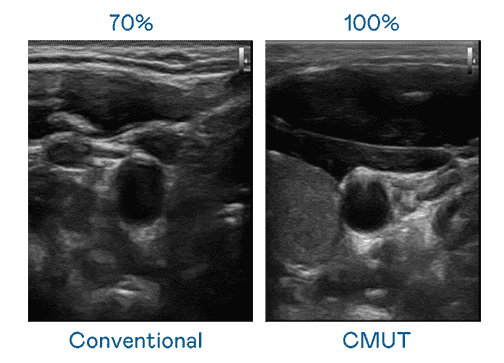

CMUT 技术是一种用电容式微机电元件来产生超音波讯号的技术。。与传统 PZT 压电式技术相比,,CMUT 频宽增加 30%,,,更宽频的超音波讯号让影像解析度大幅提升,,,是实现高影像品质医疗超音波扫描、、促进精准医疗发展的关键技术。。。。

大频宽带来超清晰影像

超音波影像的解析度高低,,,,首先取决于探头能发出的讯号频宽。。。。彩神vll CMUT 可提供高清晰的超音波讯号,,提供高频宽、、高灵敏度、、影像纹理细节更高的超音波影像,,,,协助医护人员缩短影像判读时间及利用精准的医疗影像进行诊断。。。